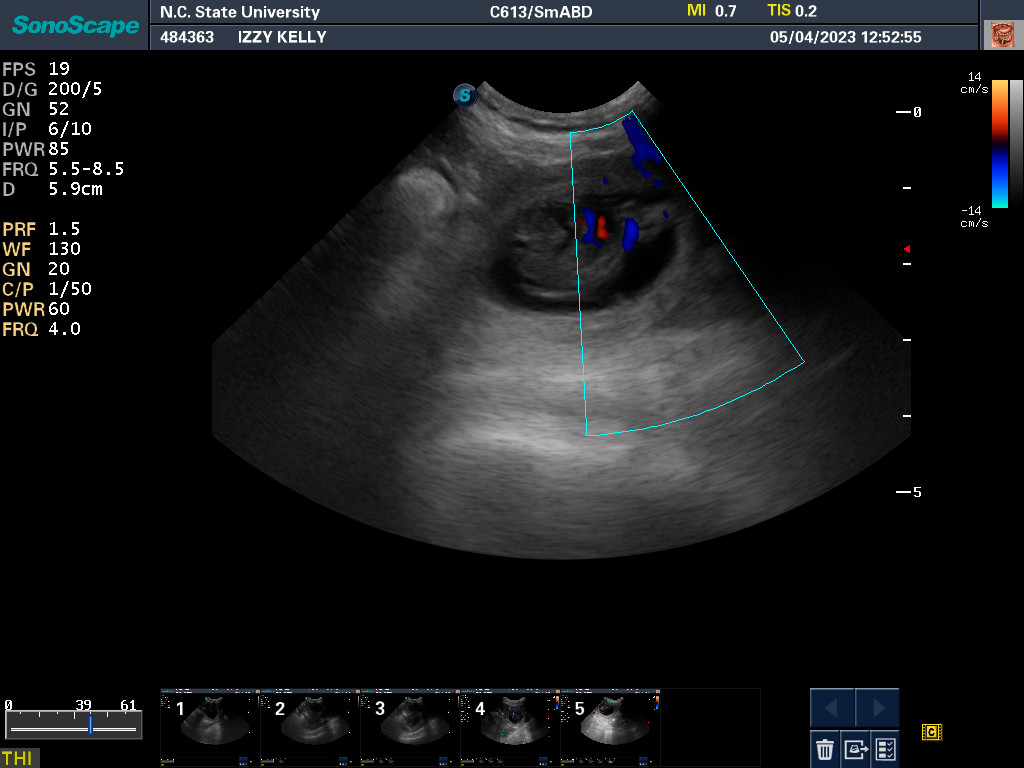

When Izzy had a dental cleaning at the beginning of the

year, the dental x-ray showed that Izzy had an impacted

tooth (a permanent tooth that had not erupted) in the

back of her mouth. My vet recommended that the tooth

be extracted, but felt that the procedure required a

dental specialist. We were able to get an appointment

with the NC State University veterinary dentistry service

in March. The day before our consultation appointment,

Izzy came into season. We kept the appointment, and the

concensus after looking at the x-rays and Izzy's mouth was

that the tooth had to come out. Since Izzy was in season

and I planned to breed Izzy (which resulted in Fergus),

it was decided to delay the surgery until after Izzy was

finished nursing any puppies.

Since Izzy is now done nursing, I contacted NC State to schedule

the surgery. I was asked to bring Izzy in for a re-check just

to make sure that there were not any changes. Today was

our re-check appointment. I brought Fergus along for

the experience and socialization.